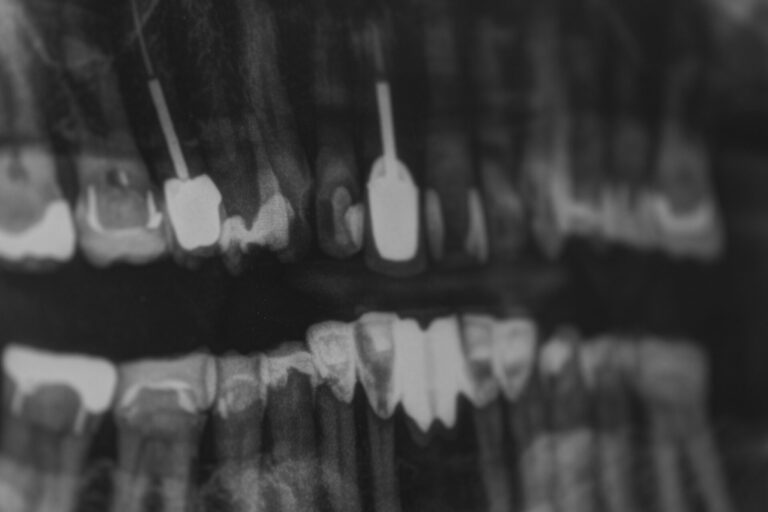

dental radiography - root canal treatment in geelong

This procedure is required when a tooth is heavily affected by decay or infection. In order to save the tooth, the pulp (living tissue inside the tooth), nerves, bacteria and any decay are removed. After cleaning and re-shaping the canal cavity, fillers are inserted to prevent bacteria from re-entering the nerve system.

Ongoing tooth pain, sensitivity or swelling can indicate infection inside a tooth. A dental exam allows our Geelong dentist to identify the cause through examination and diagnostic X-rays and determine whether treatment is required.